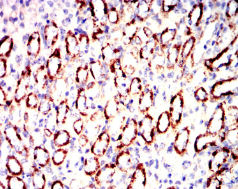

IRF3 Mouse Monoclonal antibody[5G3E2]

This gene encodes a member of the interferon regulatory transcription factor (IRF) family. The encoded protein is found in an inactive cytoplasmic form that upon serine/threonine phosphorylation forms a complex with CREBBP. This complex translocates to the nucleus and activates the transcription of interferons alpha and beta, as well as other interferon-induced genes. The protein plays an important role in the innate immune response against DNA and RNA viruses. Mutations in this gene are associated with Encephalopathy, acute, infection-induced, herpes-specific, 7.

IHC    1/200 - 1/1000